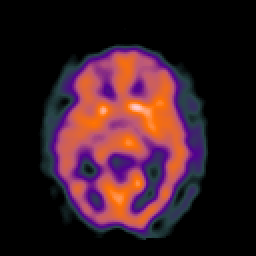

SPECT TC Study #2 -- Slice #26

[Home][Help][Clinical][Tour 1][Tour 2][Tour 3] Slice 26